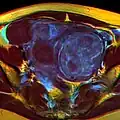

A relatively large submucosal leiomyoma; it fills out the major part of the endometrial cavity. -

MRI image with multiple uterine leiomyomas -